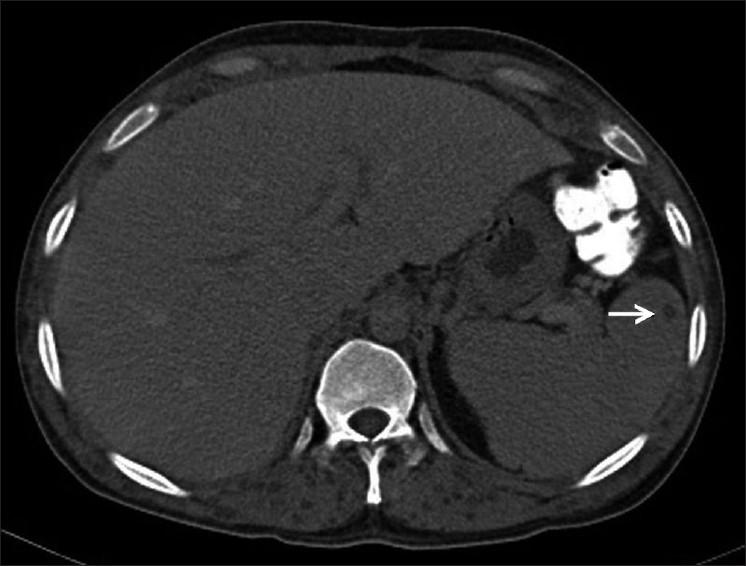

In this study, we present a case of disseminated cysticercosis involving the brain, orbit, myocardium, muscle, subcutaneous tissues, pancreas, and spleen. Imaging studies are described with emphasis on pancreatic and splenic involvement which is a rare manifestation of a rather common disease and has been radiologically demonstrated only once previously. Although the involvement of the pancreas by parasites leading to pancreatitis has been described previously, in our case there was no clinical or biochemical evidence of pancreatitis due to infection by cysticerci.

在本研究中,我们报告了一例播散性囊尾蚴病病例,累及脑、眼眶、心肌、肌肉、皮下组织、胰腺和脾脏。描述了影像学检查,重点是胰腺和脾脏受累情况,这是一种常见疾病的罕见表现,此前仅在放射学上有过一次报道。虽然之前曾描述过寄生虫累及胰腺导致胰腺炎的情况,但在我们的病例中,没有临床或生化证据表明是由囊尾蚴感染引起的胰腺炎。